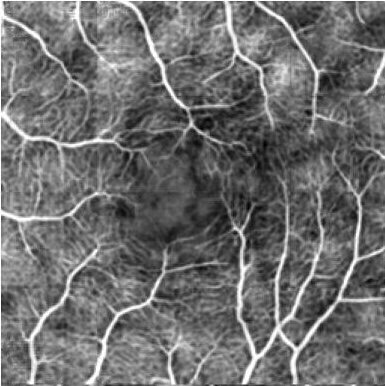

Optical coherence tomography angiography (OCTA) shows its great importance in imaging microvascular networks by providing accurate 3D imaging of blood vessels, but it relies upon specialized sensors and expensive devices. For this reason, previous works show the potential to translate the readily available 3D Optical Coherence Tomography (OCT) images into 3D OCTA images. However, existing OCTA translation methods directly learn the mapping from the OCT domain to the OCTA domain in continuous and infinite space with guidance from only a single view, i.e., the OCTA project map, resulting in suboptimal results. To this end, we propose the multi-view Tri-alignment framework for OCT to OCTA 3D image translation in discrete and finite space, named MuTri. In the first stage, we pre-train two vector-quantized variational auto-encoder (VQ- VAE) by reconstructing 3D OCT and 3D OCTA data, providing semantic prior for subsequent multi-view guidances. In the second stage, our multi-view tri-alignment facilitates another VQVAE model to learn the mapping from the OCT domain to the OCTA domain in discrete and finite space. Specifically, a contrastive-inspired semantic alignment is proposed to maximize the mutual information with the pre-trained models from OCT and OCTA views, to facilitate codebook learning. Meanwhile, a vessel structure alignment is proposed to minimize the structure discrepancy with the pre-trained models from the OCTA project map view, benefiting from learning the detailed vessel structure information. We also collect the first large-scale dataset, namely, OCTA2024, which contains a pair of OCT and OCTA volumes from 846 subjects.